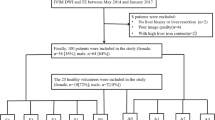

Between March 2009 and April 2012, 96 consecutive subjects with 160 FLLs were studied with both MRE and DWI. Fifty patients underwent a prospective liver MRI study with MRE for evaluation of FLLs for a clinical feasibility study on MRE. Forty six patients underwent MRI of the liver with MRE for evaluation of chronic liver disease. In these patients, MRE slices were also obtained through the FLLs, and were therefore eligible for the study. After follow-up of at least 2 years in the case of suspected benign lesions, we retrospectively evaluated the patient data. Seventeen subjects with 36 FLLs were excluded from the study for the following reasons: no histological confirmation or other supportive clinical and imaging evidence of malignancy in the case of suspected malignant lesions, failure to demonstrate stability of lesions for at least 2 years with follow-up imaging, and/or failure to follow up after initial imaging workup in the case of benign lesions without histological confirmation. The final study group comprised 79 subjects (45 male, 34 female), with a mean age of 44.8 ± 14.5 years. The FLLs included hemangioma (HEM), hepatocellular adenoma (HCA), focal nodular hyperplasia (FNH), hepatocellular carcinoma (HCC), cholangiocarcinoma (CCA), and metastasis (MET).